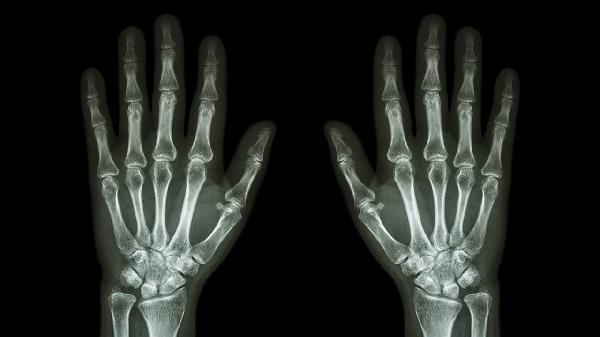

手指撞击或过度使用可能导致关节周围软组织损伤,表现为局部肿胀、压痛。急性期需立即冰敷,48小时后热敷促进血液循环。若伴随活动受限,可遵医嘱使用双氯芬酸钠凝胶、云南白药气雾剂等外用药,必要时拍摄X线排除骨折。

中老年人群因关节退变易发骨关节炎,晨起关节僵硬感明显,活动后疼痛减轻。关节超声可见骨赘形成。可遵医嘱口服硫酸氨基葡萄糖胶囊、塞来昔布胶囊等药物,配合关节腔注射玻璃酸钠改善润滑功能。

频繁屈伸手指易诱发腱鞘机械性炎症,表现为握拳时弹响伴局限性压痛。超声检查可见腱鞘增厚。早期可通过支具固定制动,顽固性病例需局部注射复方倍他米松注射液,严重狭窄者考虑腱鞘切开术。